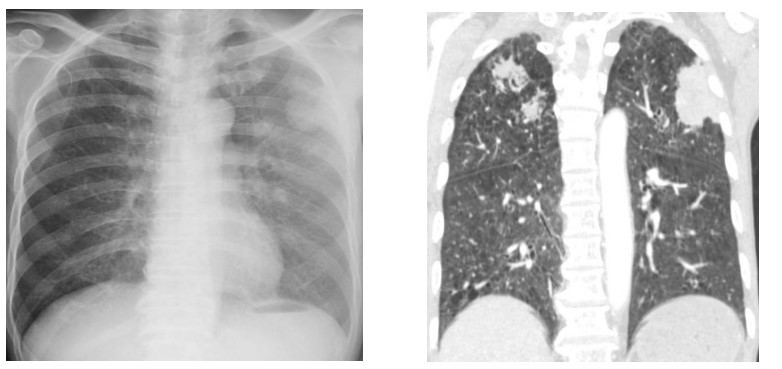

Qua kết quả xét nghiệm, bác sĩ ghi nhận người bệnh có tình trạng thiếu máu mức độ trung bình, tăng bạch cầu ái toan (một trong những chỉ điểm của tình trạng nhiễm ký sinh trùng). Đặc biệt, bệnh nhân bị viêm phổi với tổn thương dạng nốt lan tỏa cả hai bên phổi.

![]() |

| Hình ảnh phổi bệnh nhân bị tổn thương do ấu trùng giun lươn gây ra |

Trước đó, tại Bệnh viện Nhân Dân 115 cũng từng tiếp nhận nam bệnh nhân 69 tuổi, ngụ tại Tiền Giang, có tiền căn bị ung thư thanh quản, đến khám bệnh vì ăn kém, nôn ói, đau bụng, ho và khó thở trong 10 ngày. Bệnh nhân được bác sĩ kiểm tra hình ảnh và ghi nhận bị hẹp môn vị, tổn thương phổi hoại tử hai bên. Kết quả nội soi phế quản xác định, bệnh nhân bị nhiễm giun lươn.